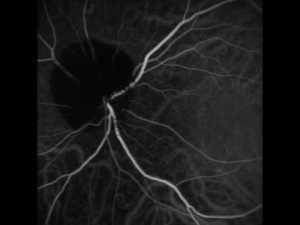

- Angiogramas, un tipo de rayos X para detectar anomalías en los vasos sanguíneos